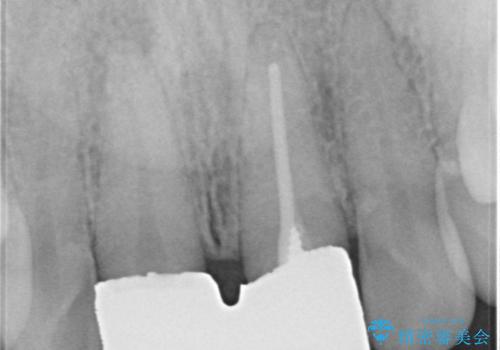

レントゲン写真より、右側の前歯は神経が失活している可能性があり、クラウン除去後に診察を行ったところ、やはり失活していました。

根管治療を行った後に、両歯ともに土台を植立し、オールセラミッククラウンにて補綴治療を行うこととしました。